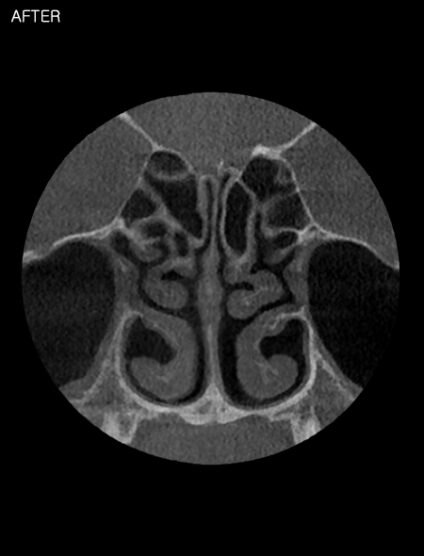

기능코성형이란? 코막힘, 비염 등의 코의 기능적 문제와 미용적인 코의 모양을 함께 개선하는 수술입니다.

코막힘은 여러 합병증을 유발하기 때문에 초기에 치료하는 것이 중요합니다. 다양한 원인으로 발생하는 비염수술은 이비인후과 전문의의 진단과 수술이 꼭 필요합니다.

비중격 교정술 시 채취되는 비중격 연골은 코성형의 좋은 재료입니다.

코성형만 한 후에 나중에 코막힘으로 인해 비중격 교정술을 받아야 하는 경우나 이미 시행한 코성형으로 비중격교정술의 난도가 매우 높아질 수 있습니다. 코성형이나 기능적 개선을 원한다면 동시에 수술을 하는 것이 유리합니다.